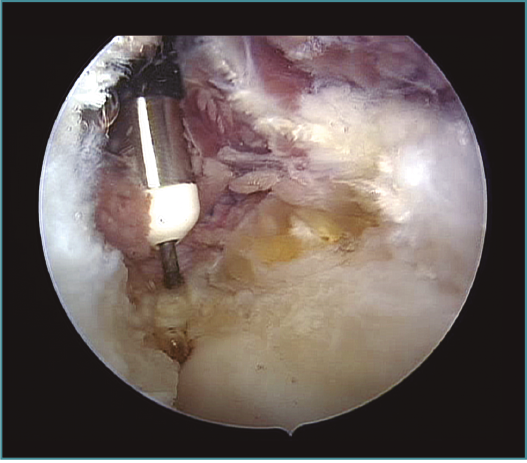

Método: hemos revisado 38 pacientes con codo rígido postraumático o degenerativo que se trataron mediante artrolisis artroscópica entre 2013 y 2016, con un seguimiento medio de 25 meses (38-15). Según la etiología de la rigidez, clasificamos a los pacientes en 2 grupos: grupo 1, los pacientes con rigidez por patología degenerativa del codo, y grupo 2, los pacientes con rigidez postraumática. Clasificamos la rigidez siguiendo la escala de Morrey y utilizamos la escala funcional Mayo Elbow Performance Index (MEPI), que evalúa el dolor, la movilidad, la estabilidad y la función del codo pre- y postoperatoriamente. Describimos los procedimientos artroscópicos realizados en cada paciente, que incluyen la sinovectomía, el desbridamiento de tejido fibroso, la capsulectomía anterior y/o posterior, la resección de osteofitos en la parte anterior y posterior del codo, la extirpación de cuerpos libres y la liberación “abierta” del nervio cubital.

Method: a review was performed on 38 patients with stiff elbow due to degenerative or post-traumatic reasons, and who were treated by arthroscopic arthrolysis between 2013 and 2016, with a mean follow-up of 25 months (38-15). Elbow stiffness was classified following the Morrey scale and the Mayo Elbow Performance Index (MEPI) functional scale was used to evaluate pain, mobility, stability and elbow function pre- and post-operatively. The arthroscopic procedures performed on each patient are described, including synovectomy, debridement of fibrous tissue, anterior and/or posterior capsulotomy, resection of osteophytes in the anterior and posterior part of the elbow, extirpation of loose bodies and open release of the ulnar nerve.